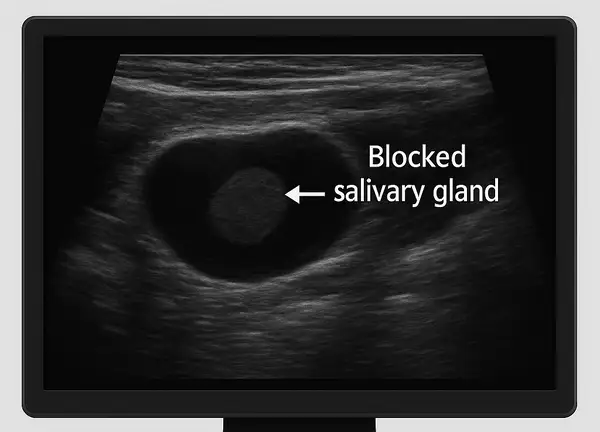

Ultrasound view used to diagnose a blocked salivary gland, illustrating how modern imaging helps detect and treat gland obstruction effectively.

Diagnostic Methods: From Ultrasound to Sialendoscopy

Ultrasound remains the first-line imaging choice due to its noninvasive nature and cost-effectiveness. CT and MRI scans help visualize deep or complex stones. The most advanced technique, sialendoscopy, involves inserting a miniature camera into the duct, allowing both visualization and immediate removal of stones — often in a single session. According to recent data , sialendoscopy boasts a 97% diagnostic success rate with minimal complications.